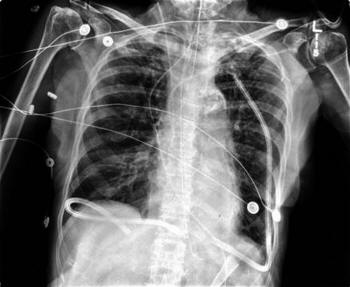

ISSN: 2233-601X (Print) ISSN: 2093-6516 (Online) Thoracic ...

Thoracic Duct Embolization for Chylothorax − 75 − Fig. 1. (A, B) Takayasu’s arteritis and a large aortic aneurysm. (C) After left subclavian artery to left commoncarotid arterial transposition ... Access This Document